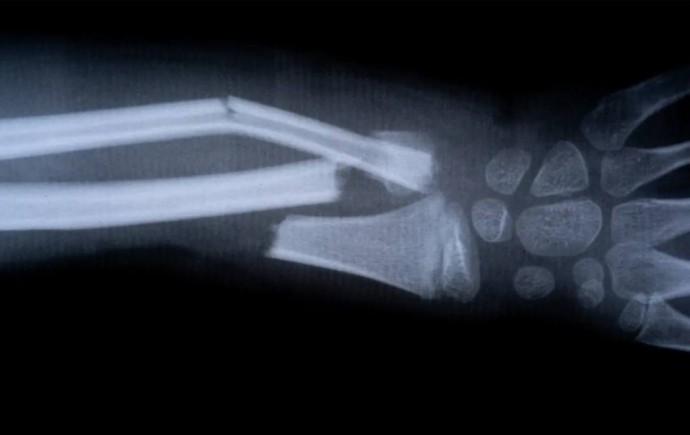

В Китае разработали суперклей для костей – он заживляет переломы за 3 минуты

Костный клей устраняет переломы всего за 3 минуты с помощью одной инъекции.

Биоинженеры из Китая совершили настоящий прорыв в ортопедии, разработав клей «Bone-02», который не боится влаги и работает даже при кровотечении, надежно соединяя между собой части костей. Клей может заменить собой традиционные металлические имплантанты, установка которых всегда связана с рисками их отторжения организмом и занесения инфекции.

Новый гель уже протестировали на 150 пациентах: вместо сложной операции по установке пластин использовали этот клей, завершив процедуру за несколько минут. Он также рассасывается самостоятельно по мере срастания кости, поэтому никаких дополнительных манипуляций для завершения лечения не потребуются.